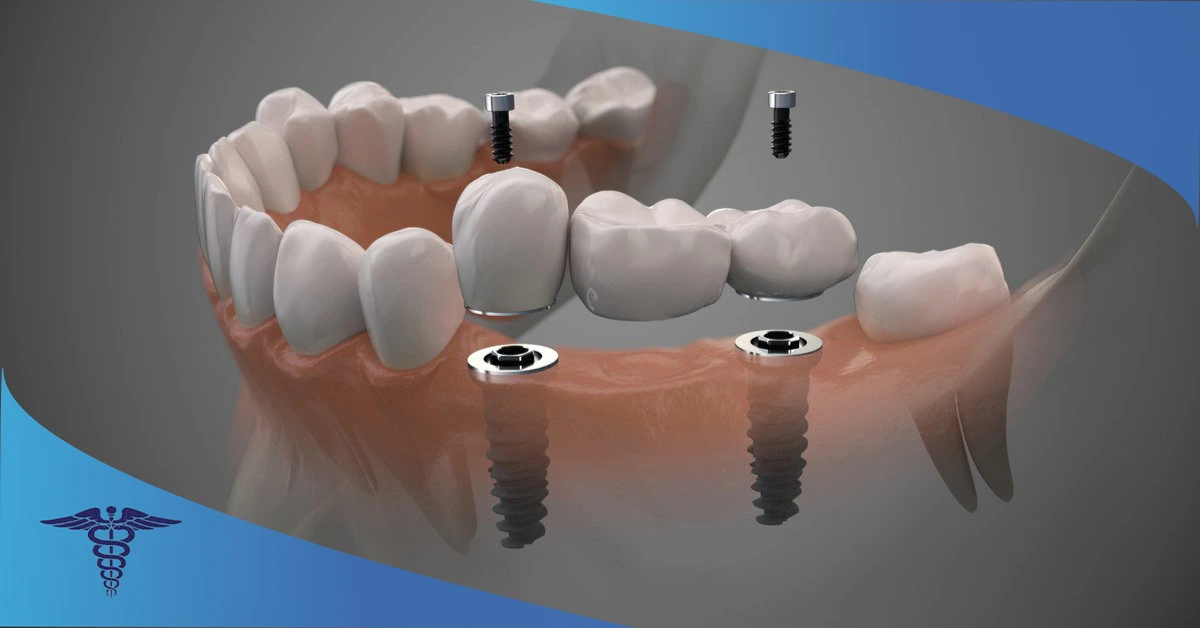

ایمپلنت دندان دیجیتال (Digital Dental Implants) به عنوان یکی از روش های دائمی برای جایگزین شدن با دندان های از دست رفته است. پیشرفت علم منجر به استفاده از روشهای جدیدی مانند ایمپلنت دندان دیجیتال برای جایگزینی دندانهای از دست رفته شده است. از نظر ساختار تفاوتی میان ایمپلنت دیجیتال با ایمپلنت معمولی وجود ندارد، فقط برای کاشت ایمپلنت دیجیتال در شیراز از تجهیزات اختصاصی برای اسکن داخل دهانی و تعیین دقیق محل جایگذاری فیکسچر استفاده می شود.

ایمپلنتهای دیجیتال معمولا از تیتانیوم ساخته میشوند. این فلز سازگاری بسیار خوبی با بدن انسان دارد، کاملاًخنثی است و هیچ حساسیتی در بدن شما ایجاد نمیکند. در ایمپلنت دیجیتال، تیتانیوم در استخوان فک شما قرار میگیرد و یک تاج دندان روی آن قرار میگیرد. با گذشت زمان بیشتر و پیوند بهتر بین ایمپلنت و فک، میتوانید به راحتی از دندانهای جدید خود لذت ببرید و بدون هیچ مشکلی یک ایمپلنت زیبا داشته باشید.

مرحله پنجم: ساخت روکش دندان 🦷

سپس دندانهای جدید شما را با استفاده از فناوری CAD/CAM ساخته می شوند. این کار ممکن است چند ساعت تا چند روز طول بکشد. در این مرحله باید حتما رنگ مناسبی را برای روکش دندانی خودتان انتخاب کنید تا پس از کاشت زیبایی لبخند شما نیز تامین شود.

مرحله ششم: نصب روکش روی دندان 😁